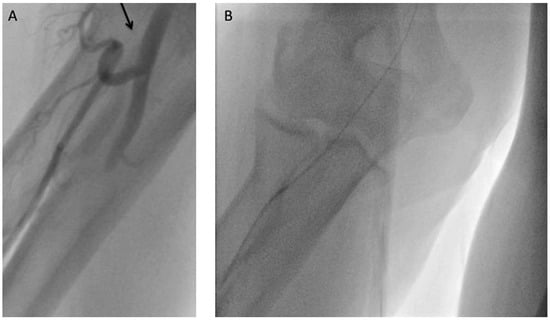

Case report. A 63-year-old hypertensive male presented with atypical chest discomfort and breathlessness on exertion [...]